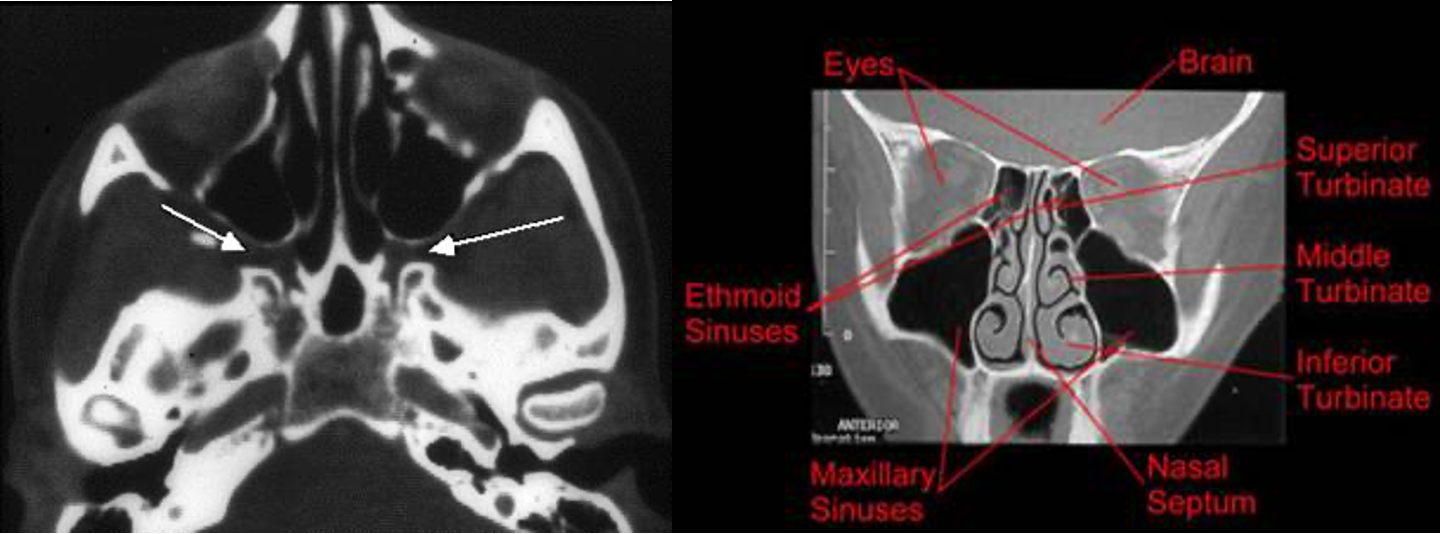

The Maxillary Sinus

- Sinus ostium located in the middle meatus

The Ethmoid Sinuses

- Anterior ethmoids: drain into the middle meatus

- Posterior ethmoids: drain into superior meatus